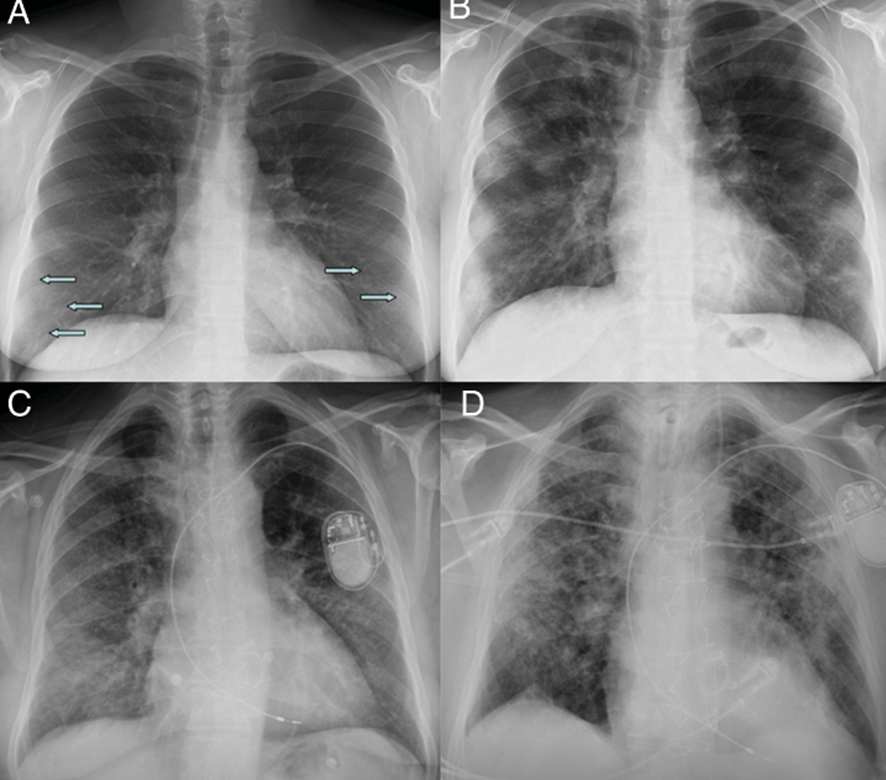

Radiografía inicial (A) y a los 12 días (B) en paciente con COVID-19 y enfermedad moderada. En la radiografía inicial se aprecian opacidades sutiles “en vidrio deslustrado” de localización periférica en campos pulmonares inferiores (flechas). A los 12 días, se observan consolidaciones multifocales de predominio periférico. Radiografía inicial (C) y a los 20 días (D) de otro paciente con COVID-19 y enfermedad moderada, en la que se observan inicialmente opacidades “en vidrio deslustrado” en bases y región periférica de campos medios y superiores, que progresan a un patrón alveolointersticial grosero que predomina en la región periférica de campos medios y superiores